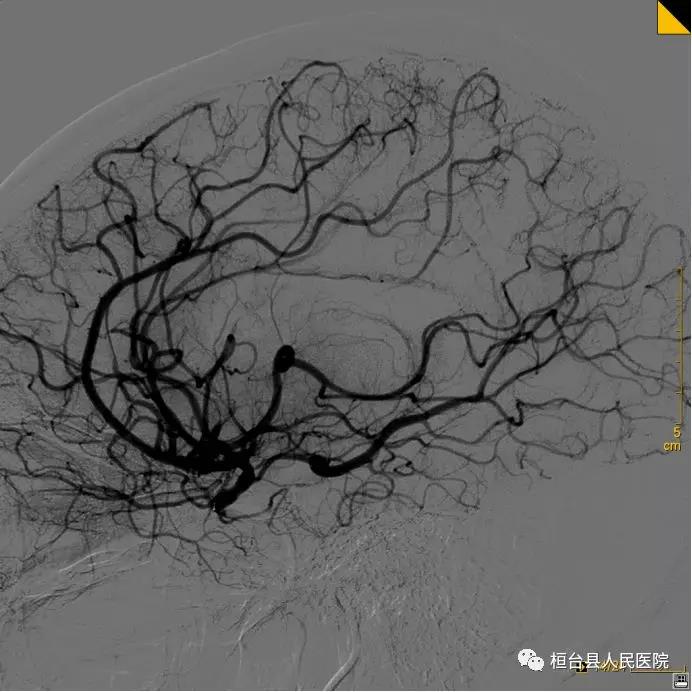

患者被送至介入导管室,神经内科王克水副主任医师与许业宦主治医师立即为其进行急症脑血管造影,发现患者右侧颈内动脉在颈部就闭塞了,无法给右侧大脑供血,需要开通闭塞血管恢复大脑供血。由于距离发病时间偏长,血栓较之前增大,手术难度也大大提升。神经内科团队通过导管抽吸和支架取栓的方法,从患者颈部到颅内逐渐开通了闭塞血管,恢复了大脑血流,手术成功。目前患者病情稳定,逐渐康复。

术前血管造影 血管开通,大脑血流恢复